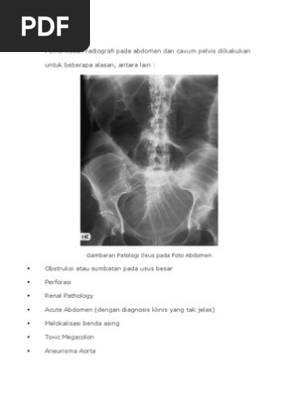

Diagnosis Ileus Obstruktif Alomedika. Symptoms may include severe pain, swelling of the abdomen, fever. The inflammation is usually the result of a fungal or bacterial infection. Peritonitis is inflammation of the peritoneum, the thin layer of tissue covering the inside of your abdomen and most of its organs. Peritonitis is inflammation of the peritoneum, the lining of the inner wall of the abdomen and cover of the abdominal organs. Consumer information about peritonitis, including spontaneous bacterial peritonitis symptoms like abdominal pain, nausea, vomiting, diarrhea, fatigue, constipation, and unexplained mental changes. Peritonitis — comprehensive overview covers causes, symptoms, treatment of this abdominal infection. • peritonitis does not necessarily always imply infection: This can be caused by an abdominal injury, an underlying medical condition, or a treatment device. Peritonitis in obstetrical practice most often develops after cesarean section. Sometimes, peritonitis develops as a complication of liver disease, such as cirrhosis, or of kidney disease. Bno 3 posisi definisi bno 3 posisi adalah prosedur pemeriksaan radiografi pada daerah abdomen khususnya untuk memperlihatkan kelainan yang terjadi pada tractus digestivus / gastrointestinal yang dilakukan dalam 3 posisi pemotretan (biasanya pada kasus abdomen akut). Pada peritonitis dilakukan foto polos abdomen 3 posisi, yaitu : It is caused by a violation of the barrier function of the. Causes, types, and treatment options for peritonitis is provided. Chronic form of peritoneal inflammation most often due to peritoneal dialysis resulting in severe fibrotic thickening of both visceral and parietal peritoneum.